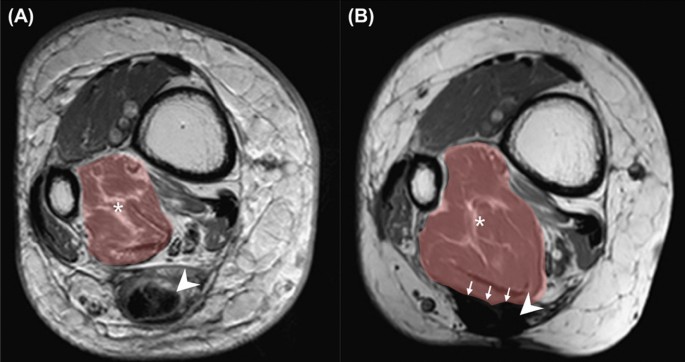

Cross-section of lower limb at the selected level at 80 mm above the myotendinous junction in MRI before and after FHLT from the same case (No. 5, in reattachment group, and the postoperative image was obtained 19 months after index surgery). (A) Preoperative and (B) postoperative T1W MRI. Cross-sectional area of the FHL muscle belly demonstrated by brown shadow. Asterisk: Fat infiltration in FHL muscle belly area in coronal section. Arrowhead: Achilles tendon. Arrow: the integration between FHL and the reattached site of the Achilles stump.